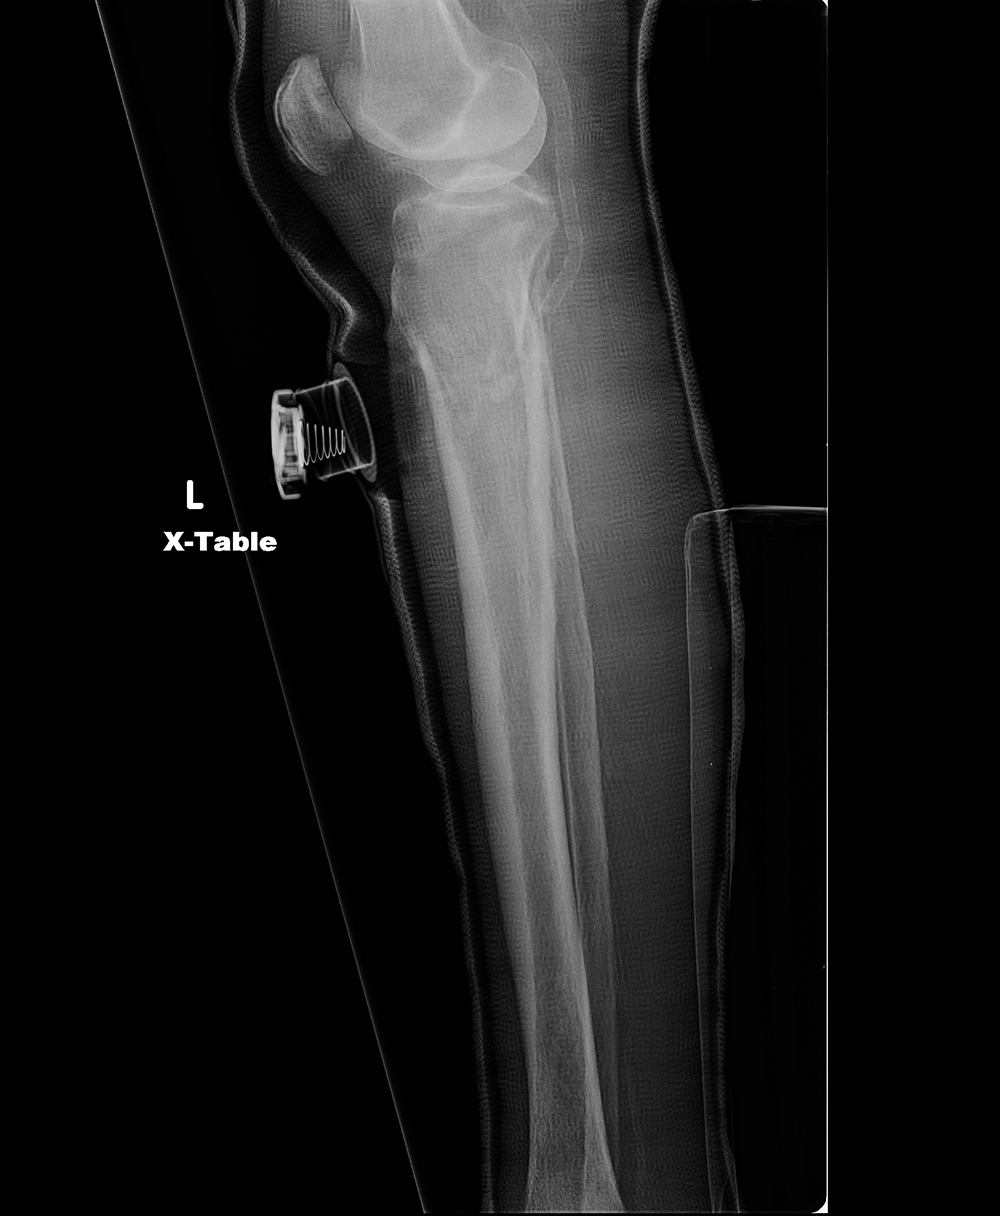

71-year old woman with left proximal tibia and fibula fractures with delayed healing. A bone stimulator was placed to enhance bony healing. Courtesy Kellon Hansen, MD.